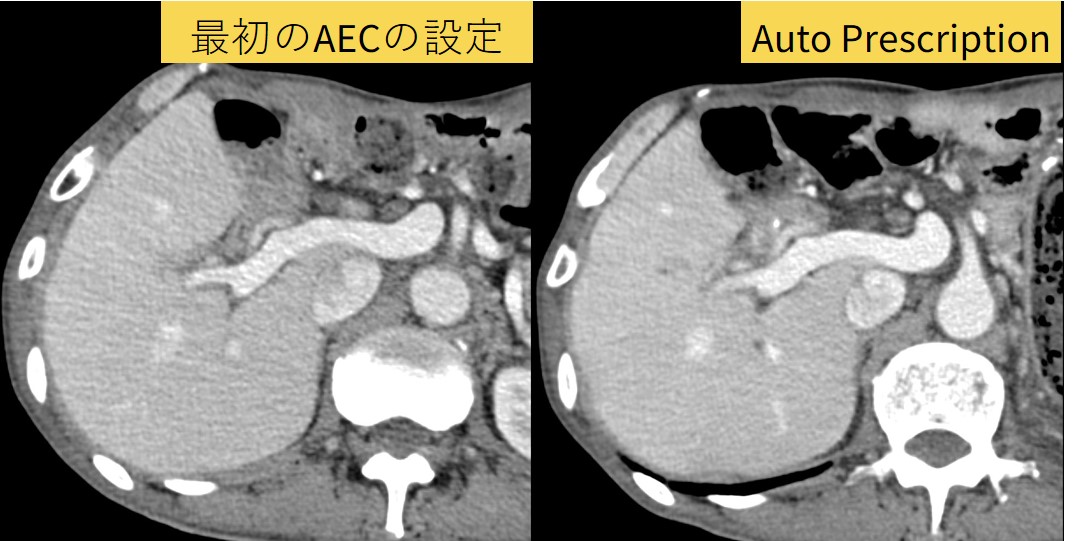

Auto Prescriptionは、事前に患者体型ごとにmAやPitchなどの撮影条件を設定しておくことで、実際のスカウト画像から装置が撮影条件を自動選択する機能です。この機能により選択の幅が広がり、体型に応じた設定ができるため最初の設定ではノイジーに感じていた体型でも納得のいく画質に設定変更することができました。

Fig2. Auto Prescriptionを用いて、撮影者に依存せず、やせ型の患者にも最適な線量で撮影が可能